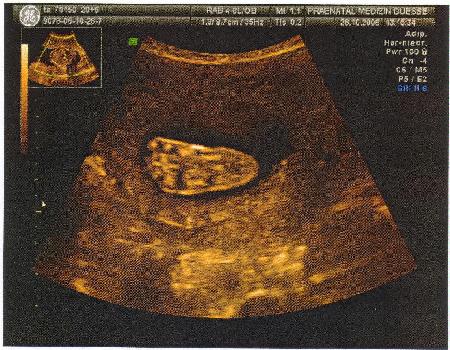

21.Woche